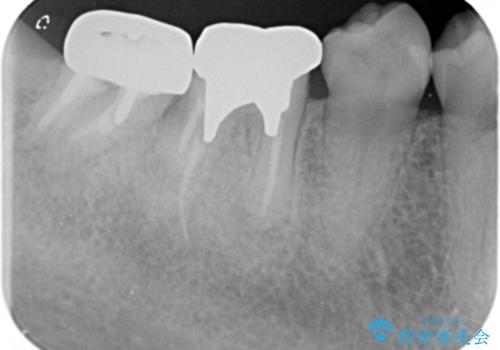

- 「笑った時に目立つ奥歯の銀歯を外して白くしたい。」と希望され来院されました。

金属のクラウンは薄く加工しても壊れないことがメリットですが、セラミッククラウンを装着するにはスペースが少なすぎ、このまま治療を進めると外れやすく壊れ易いセラミッククラウンの設計となるため、歯周外科を行い狭小なスペースの拡大を行うこととしました。